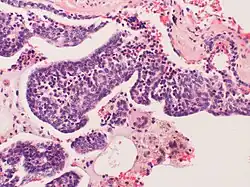

Células neuroendócrinas são neurónios especializados, capazes de produzir e libertar hormonas e neurotransmissores no sangue. Geralmente situam-se no sistema nervoso, mas podem ser observadas em vários órgãos e sistemas.[1]